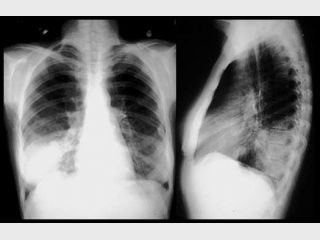

Все жертвы вируса на Буковине (22 человека в возрасте от 20 до 40 лет) умерли не от двусторонней пневмонии, как это считалось ранее, а в результате вирусного дисстрессиндрома, то есть тотального поражения легких: сначала наступает сердечно-легочная недостаточность, а затем развивается кардиогенный шок, который вызывает остановку сердца и смерть. Об этом 11 ноября газете "Доба" сообщил начальник бюро Черновицкой областной судмедэкспертизы, доктор наук, профессор Виктор Бачинский, пишет ВОВРЕМЯ.

"Во время двусторонней пневмонии отслеживается определенная морфологическая картина. Относительно данных смертей, то здесь такой морфологической картины нет. Вирус, который вызывает смерть, очень агрессивен, он даже не поражает трахею, а сразу попадает в легкие и вызывает сильный их отек и сплошные кровоизлияния. Вызывают такое состояние смешанные типы парагриппа и гриппа А/Н1N1. Это очень токсичный штамм, который до сих пор не подвергался выработанной Минздравом методе лечения", — сообщил Бачинский.

По его словам, нужно срочно менять стандарты лечения, ведь те, которые применялись до сих пор, результатов не дали — в реанимации не удалось спасти всех людей, пораженных этим вирусом. Не оправдались в этой ситуации и аппараты искусственной вентиляции легких — смертность людей наступала в 100%.